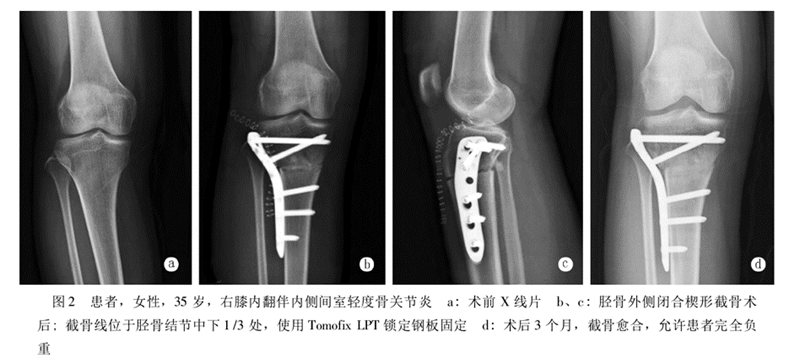

选择不同的内固定,临床结果不尽相同。一组使用门型钉作为内固定的HTO病例,7.5年随访的满意度仅有60%;使用角钢版作为内固定的HTO病例,8.4年的随访满意度为61.1%;使用非锁定型Puddu钢板作为内固定的HTO病例,其并发症发生率高达43%;使用Tomofix锁定钢板作为内固定的病例,6.5年满意度高达98.5%。

北京积水潭医院黄野教授等采用改良外侧闭合楔形胫骨高位截骨术治疗24例共35膝年龄均在45岁以下的膝内翻伴膝关节内侧间室轻度骨关节炎患者,术后平均胫股角(FTA)173.6°±2.4°,平均矫正11.0°±4.3°,截骨端均愈合,有1例延迟愈合。术后半年完全负重,无一例发生感染。2例出现腓总神经并发症(5.7%)。

采用改良外侧闭合楔形截骨,可以安全有效纠正内翻畸形,缓解骨关节炎疼痛,适用于年轻活跃的单侧或双侧膝内翻患者。但腓骨截骨的并发症仍然是需要考虑的因素之一。

病例

病例1:46岁,滑雪运动员,多发韧带伤,内翻畸形膝关节疼痛,开式截骨后二月全负重行走,膝关节疼痛缓解